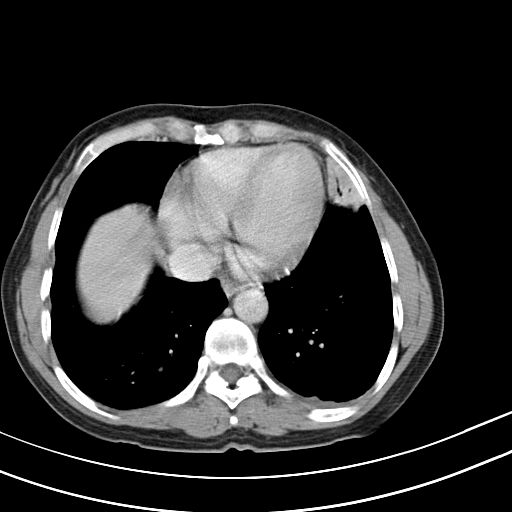

女,47岁,咳嗽胸痛一个星期,我们考虑肺结核,左下肺病灶肿瘤像不像,请高手指点。急。

右肺考虑炎症,建议抗炎后复查,左肺下叶考虑肺不张。

考虑炎性病变,左肺舌叶病灶需要与早期肺脓肿鉴别(结合实验室),左侧少量胸腔积液。

左上肺舌叶实质性病变,形态呈楔形,内可见支气管气像,中至重度强化,考虑为炎性改变,建议复查

左肺舌叶病灶呈扇形分布,其内可见支气管影,胸膜面光滑,不支持肿瘤病变。